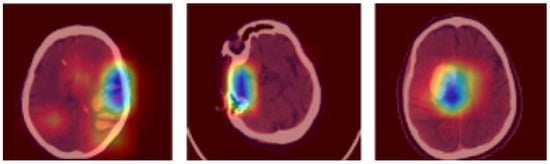

where and indicates the degree of membership of the iterations and , and specifies the highest vector value. Furthermore, the hybrid feature extraction is accomplished using HoG, LBP, and LTP descriptors for extracting features from the segmented images. The sample segmented 3D brain scans are depicted in Figure 3.

Figure 3.

Sample segmented 3D brain scans.